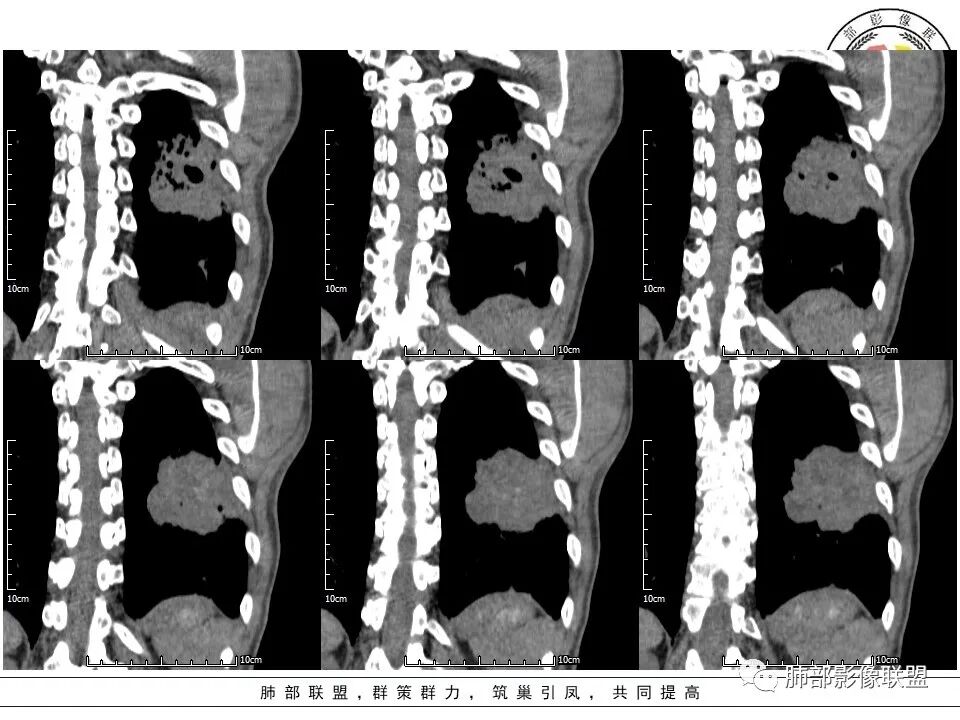

2、左肺下叶近胸膜下较大肿块,土豆样外形,边缘清楚,膨隆分叶,未见明显渗出;病灶内部多坏死及空洞,似鬼脸征,坏死边界不清;增强扫描轻度不均匀环形强化;近端支气管似有阻塞截断。肺门纵隔未见肿大淋巴结。

3、综上所述,考虑恶性,鳞癌可能。

胸CT:肺气肿背景,双肺下叶背侧蜂窝影,左肺下叶肿块影,位于交界地带,边缘清,膨隆、分叶,内有多发厚壁空洞(重叠在蜂窝背景上,不敢确定真实性),洞壁光滑,内有多灶性坏死,支气管在肿物边缘截断,胸膜局部增厚,中度强化。考虑:恶性肿瘤,鳞?肉瘤?鉴别TB、隐球等。

7、可宽基底与胸膜相连征,容易侵及壁层胸膜以外形成“栽赃”。与腺癌相比,病灶收缩能力不强,即便有棘状突起及胸膜牵拉,张力也没那么高。